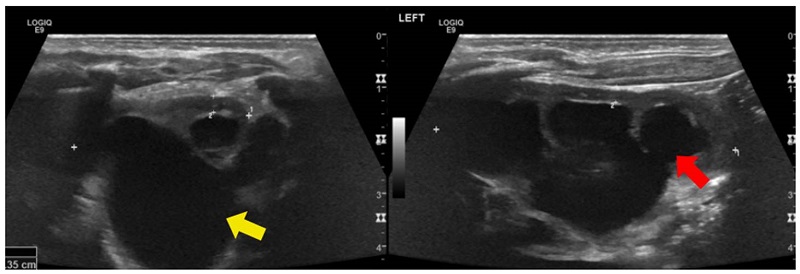

Se trató de un paciente de sexo masculino, producto de una unión consanguínea, que a los seis meses de vida presentó un episodio de pielonefritis. La ecografía renal mostró imágenes sugestivas de enfermedad poliquística renal autosómica recesiva, con múltiples imágenes quísticas bilaterales de ecogenicidad heterogénea y pérdida de la diferenciación corticomedular (figura 3). No presentaba lesiones hepáticas en la ecografía y la función hepática era normal.

A los cinco años de vida, una junta médica de genética clínica consideró que se trataba de una secuencia de obstrucción temprana de las vías urinarias (riñón multiquístico, diástasis de rectos abdominales y criptorquidia bilateral), con antecedentes familiares de consanguinidad parental, lo que sugiere una enfermedad poliquística renal de herencia autosómica recesiva. En un panel de secuenciación de nueva generación de los genes PKD1, PKD2 y PKHD1, no se encontraron variantes patogénicas en estos, por lo que se solicitó secuenciación de exoma en trío, actualmente en proceso.

Análisis. La enfermedad poliquística renal de herencia autosómica recesiva es una condición rara y de presentación usualmente grave en los primeros años de vida. Su incidencia se ha reportado como un caso por cada 26.500 recién nacidos vivos 18. Representa un espectro clínico que incluye la presencia de quistes que afectan los conductos colectores, así como nefromegalia, pérdida de la diferenciación corticomedular y fibrosis hepática; es causada principalmente por variantes bialélicas del gen de la fibrocistina (PKHD1), aunque también se han reportado variantes del gen DZIP1L (DAZ interacting protein 1-like) 19. Sin embargo, existe un gran número de síndromes con presentaciones similares (fenocopias), por lo cual se indica el diagnóstico molecular mediante secuenciación masiva paralela de múltiples genes. Se estima que en el 20 al 25 % de los pacientes no se encuentra la causa genética 20.